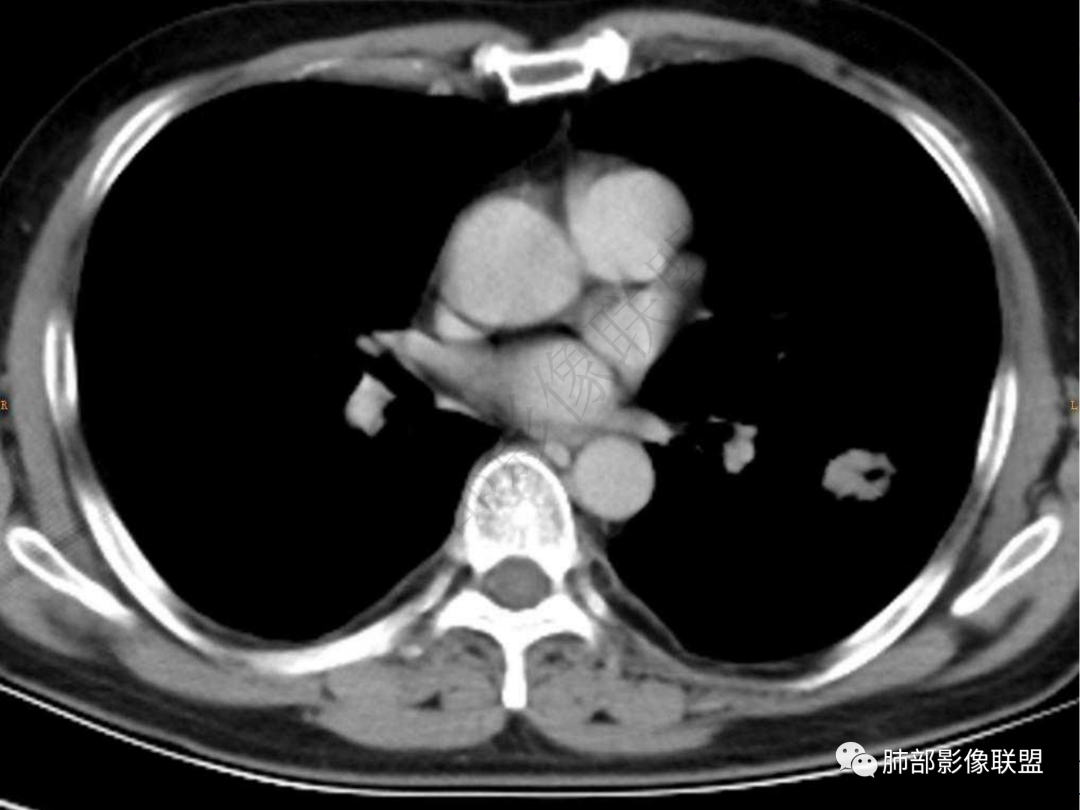

2.左肺下叶团片影,跨背段及内前基底段,实性部分类椭圆形,密度不甚均匀,可见毛刺及棘状突起,未见典型分叶及胸膜凹陷。病灶上下缘可见相应肺段支气管旁进侧出,管壁轻度增厚,未见狭窄阻塞。

3.周边较大范围磨玻璃影,边界相当模糊,小叶增厚明显。注意叶裂另一侧、左肺舌段亦可见磨玻璃影及增厚的小叶间隔。未见明确卫星病灶。

4.实性部分不均匀环形强化并显示一小范围低密度坏死区或空洞。较之肺窗,整体纵隔窗范围较小,提示病灶并不十分密实。抑或为不同时段图像。

5.双肺门及纵隔未见增大淋巴结。未见胸腔积液。